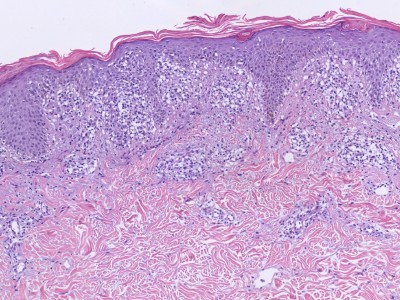

Diagnostiek:

De diagnose wordt gesteld op het klinisch beeld. Soms is een luesserologie nodig

voor de DD. Zonodig een biopt afnemen (als het klinisch toch niet duidelijk

herkenbaar is als pityriasis rosea).

![Histologie pityriasis rosea (click on photo to enlarge) [source: Kevin Kwee / Afdeling Pathologie MUMC] Histologie pityriasis rosea](../../../pacoupes/thumbnails/pityriasis-rosea-1.jpg) |

![Histologie pityriasis rosea (click on photo to enlarge) [source: Kevin Kwee / Afdeling Pathologie MUMC] Histologie pityriasis rosea](../../../pacoupes/thumbnails/pityriasis-rosea-2.jpg) |

|

ingescande coupe (zoom) |

Bron

hoge resolutie PA-foto's: Kevin Kwee en Afdeling Pathologie MUMC. Klik

op de afbeelding om in te zoomen.